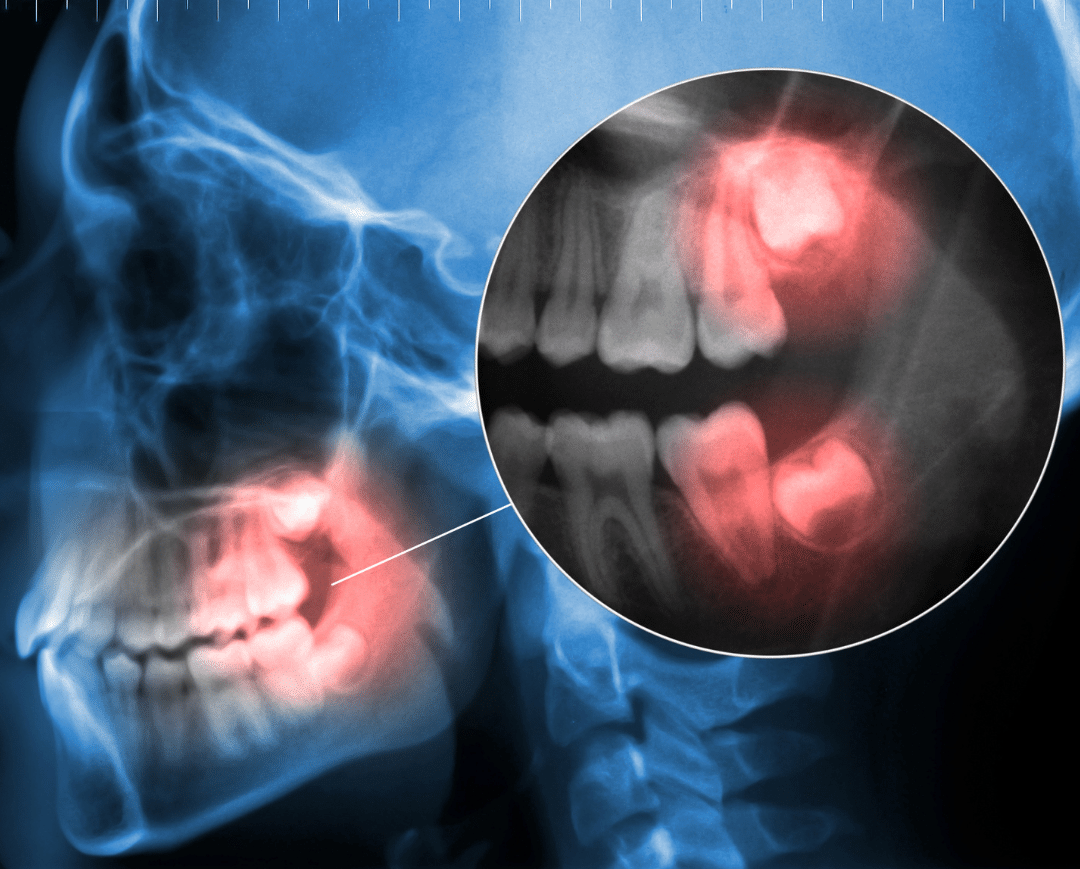

Impacted teeth can often be diagnosed during a routine dental examination. Dentists may use a variety of tools and techniques to identify impacted teeth, including X-rays, CT scans, and visual examination of the mouth.

According to the American Association of Oral and Maxillofacial Surgeons, impacted teeth can be detected through a combination of visual examination, X-rays, and CT scans.

X-rays and other imaging tests play a crucial role in determining the most effective extraction method. The type of imaging test used will depend on the location and position of the impacted tooth. Common imaging tests include panoramic X-rays, cephalometric X-rays, and cone beam computed tomography (CT) scans. These tests help your dentist or oral surgeon visualize the impacted tooth and surrounding tissues, allowing them to plan the extraction procedure accordingly.

A panoramic X-ray provides a general view of the jaw and teeth, while a cephalometric X-ray focuses on the relationship between the teeth and jawbone. A cone beam CT scan provides detailed, three-dimensional images of the impacted tooth and surrounding tissues.